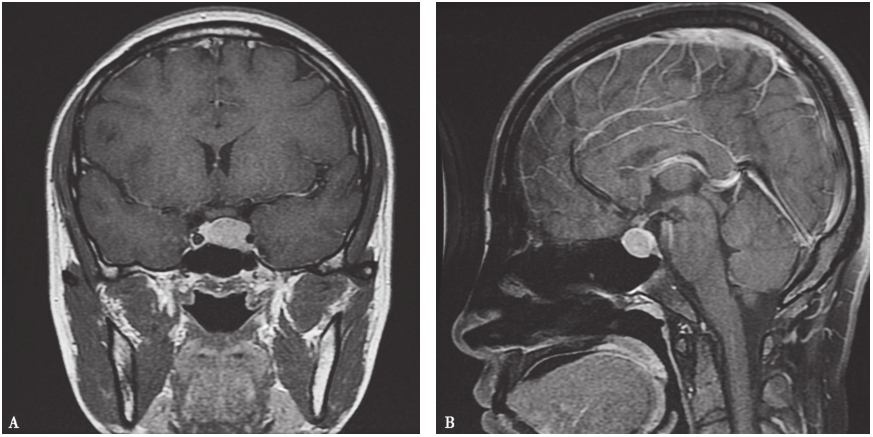

因FGAs起病相对隐匿,故多数患者表现为垂体大腺瘤甚至是巨腺瘤,如图1所示为北京协和医院诊治的1例女性FGAs的垂体MRI。

图1 垂体增强扫描MRI

A.冠状位;B.矢状位

鞍内可见类圆形低信号影,病灶大小约2.3cm×1.4cm;增强扫描示病灶轻度强化,正常垂体受压变薄,垂体柄冠状位显示欠清晰,病变侵犯左侧海绵窦,右侧海绵窦未见明显异常。